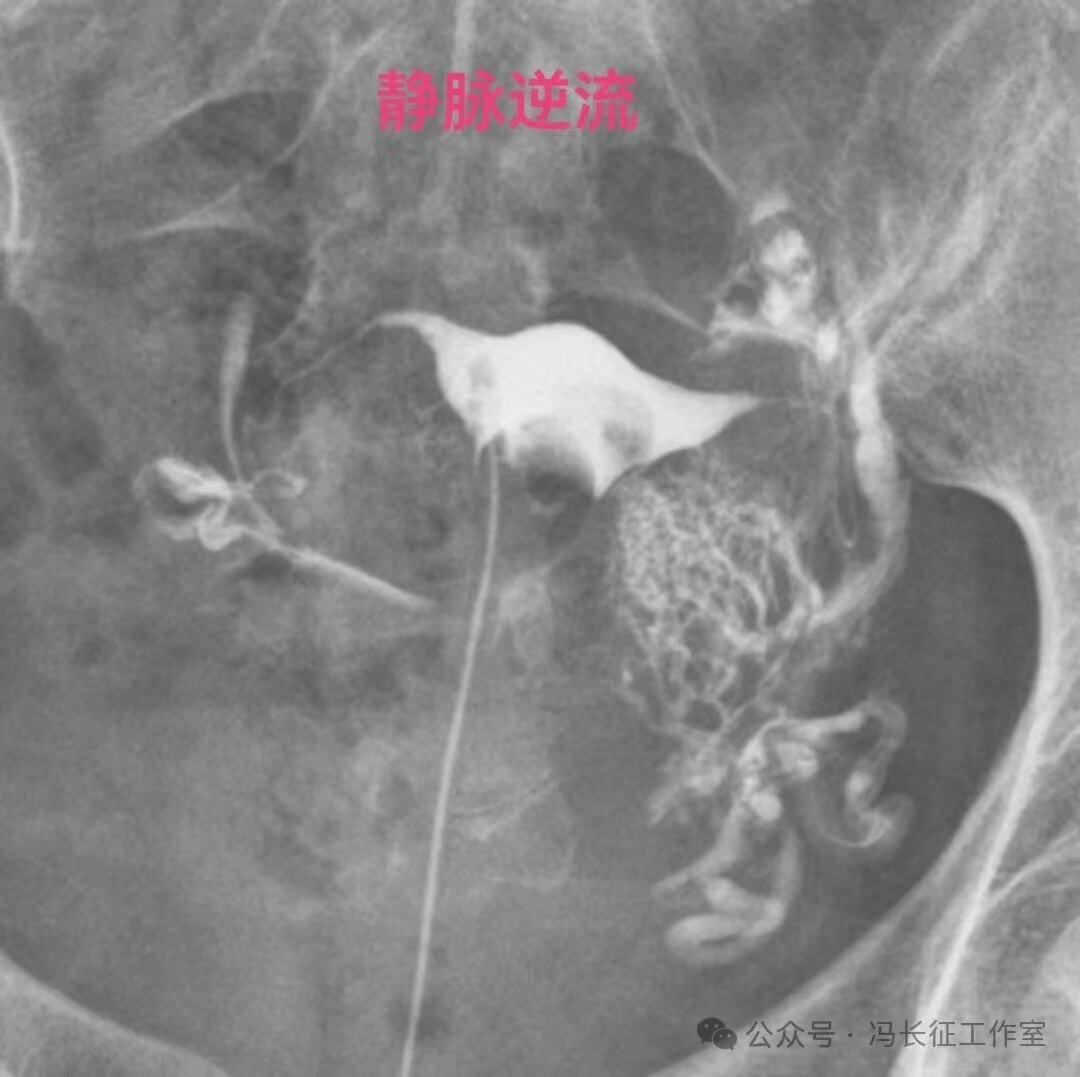

造影剂逆流可以进入静脉和淋巴管,逆流分三种:(1)淋巴逆流;(2)静脉逆流;(3)淋巴和静脉混合性逆流。其实,一般多是静脉和淋巴都有的混合性逆流,淋巴逆流是造影当时以淋巴逆流为主,同时有少量的静脉逆流,本来淋巴管后来就是要汇入到静脉的。静脉逆流也是以静脉逆流为主,同时有少量的淋巴逆流。